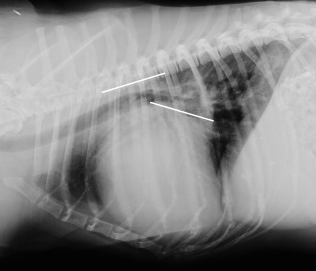

DICOM viewer를 볼때 VHS의 불편함을 줄이기 위해 여러 지표들이 나오고 있는데 이번 소개되는 논문에서는

심장의 장축과 단축을 각각 척추체의 길이로 치환하는게 아니라

두 숫자의 크기를 합하여 척추체 4~8번을 각각 나눴을때 VHS와 어느정도 상관성을 갖는가에 대한 논문이다.